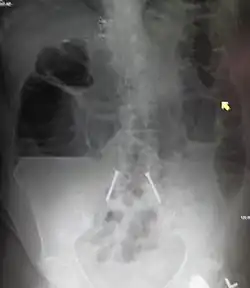

| Upright abdominal X-ray demonstrating a small bowel obstruction. Note multiple air fluid levels. | |

Radiological signs of bowel obstruction include bowel distension (small bowel loops dilated >3 cm) and the presence of multiple (more than 2) air-fluid levels on supine and erect abdominal radiographs.[16] Ultrasounds may be as useful as CT scanning to make the diagnosis.[17]